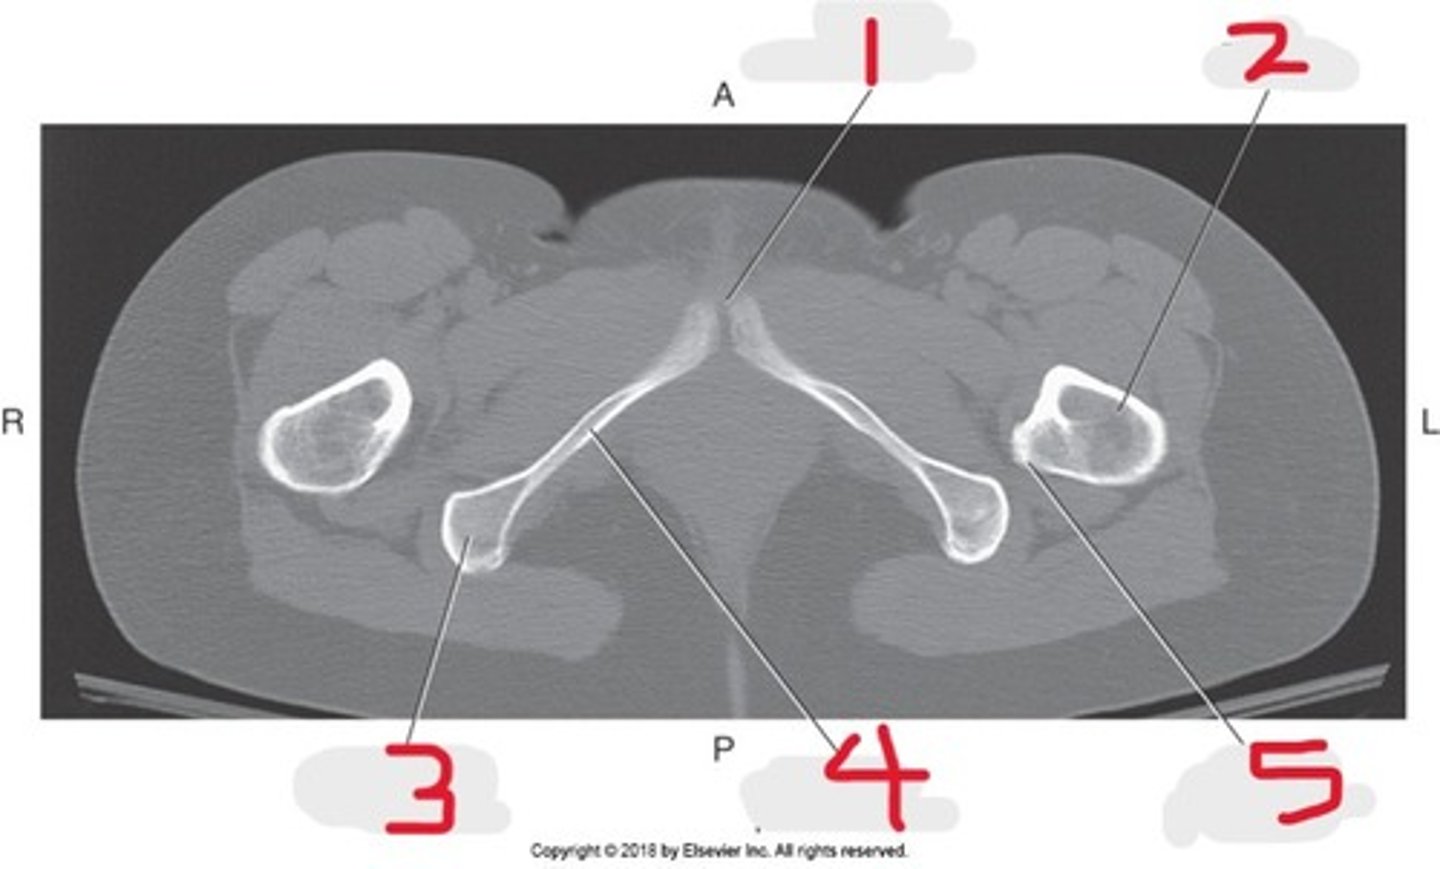

1) Body of pubic bone

2) Pubic symphysis

3) Greater trochanter

4) Anus

5) Ischial tuberosity

Name all numbered structures

1) Pubic symphysis

2) Femur

3) Ischial tuberosity

4) Inferior pubic ramus

5) Lesser trochanter

Name all numbered structures